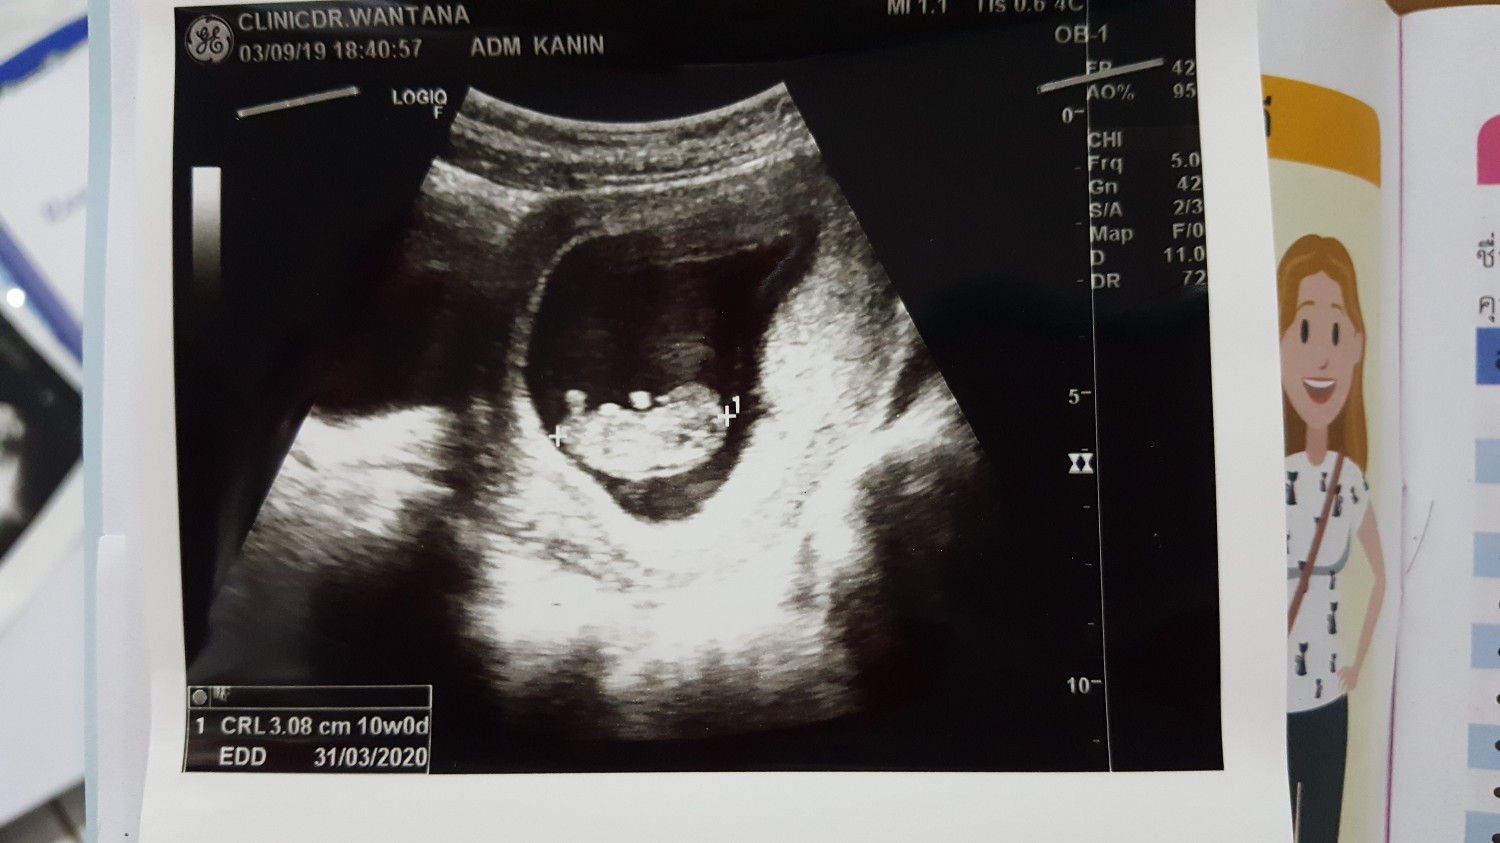

ดูรูปอัลตร้าซาวด์ให้หน่อยค่ะ แบบนี้ถือว่าค่า nt หรือความหนาบริเวณต้นคอหนามั้ยคะ

อายุครรภ์  11 สัปดาห์ค่ะ  พึ่งไปซาวด์มา  แต่ไม่เห็นหมอว่ายังไง เราก็พึ่งได้ทราบข้อมูลคร่าวๆจากในเน็ต ว่าสามารถคัดกรองดาวซินโดรมด้วยการหาค่า nt ได้  จิตตกค่ะ พะวง นอนไม่หลับ